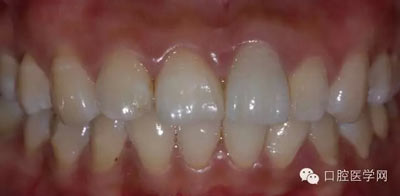

8、術(shù)前術(shù)后對比